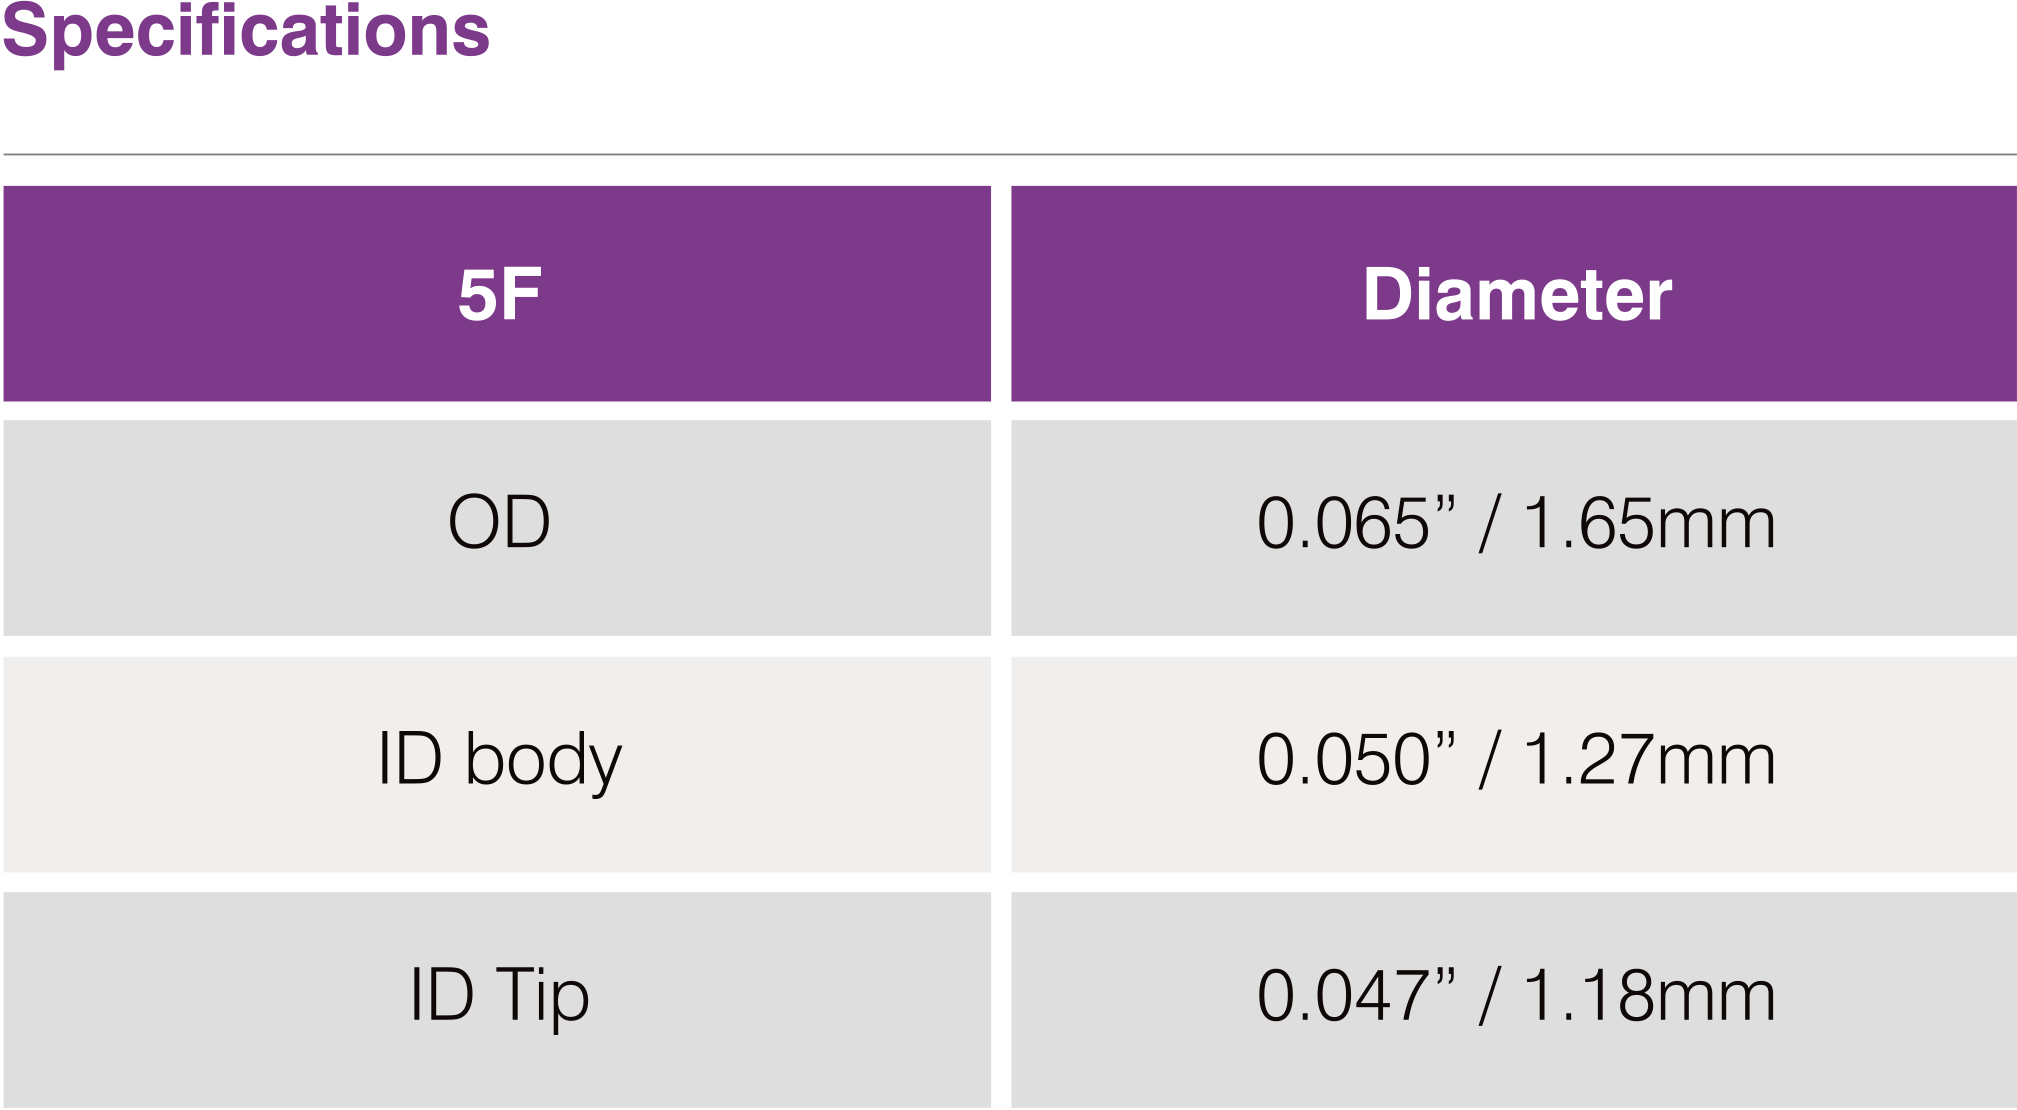

Radial Diagnostic Catheter

Features & Benefits

-

Enables angiography of both RCA and LCA with one catheter that can potentially:

• Eliminates a catheter exchange step

• Shorten procedure & fluoroscopic time

• Lower cost per procedure - Engages with simple clockwise & counter clockwise rotation

- Soft tip reduces potential for vessel trauma

- High Flexibility

- Superior Surface Smoothness

- Excellent 1:1 Torque Control due to double wire stainless steel braiding

- Large inner lumen for superior flow rates

- Atraumatic soft tip

- Guidewire Compatibility : 0.038”/ 0.97mm

- Max Pressure : 1200 PSI / 84 bar